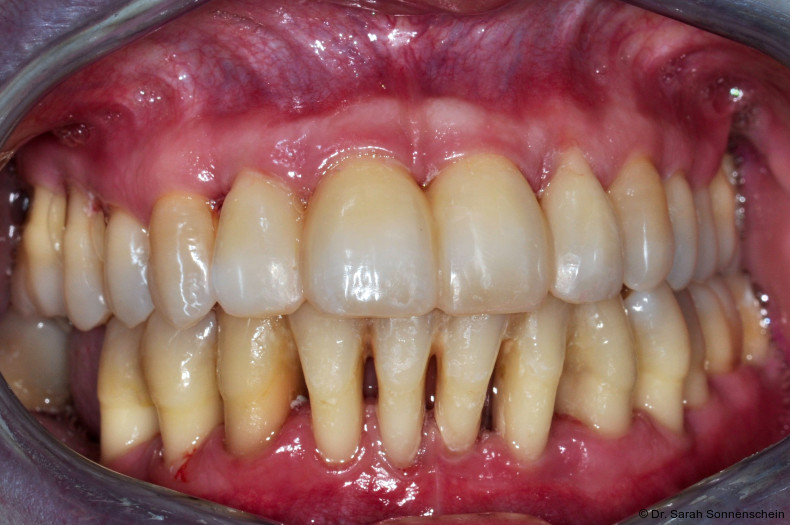

Die Abbildungen 2a–d zeigen die Eingangssituation einer allgemeinmedizinisch gesunden 37-jährigen Nichtraucherin mit Parodontitis Stadium IV Grad C, Falltyp 1 (damalige Diagnose: generalisierte aggressive Parodontitis). Ihr Hauptanliegen war der Zahnerhalt und die Beseitigung der „lockeren“ Zähne. Die Sondierungstiefen lagen generalisiert zwischen 5 und 9 mm. Die AV bei bis zu 12 mm. Die Zähne 33-43 wiesen alle einen Lockerungsgrad III auf. Auch die Oberkieferfront wies einen Lockerungsgrad II auf. Nach der Mundhygienephase erfolgte eine Full-Mouth-Disinfection mit adjuvanter Antibiotikagabe. Die Schienung der Zähne 33-43 erfolgte mittels glasfaserverstärkter Kompositverblockung. Bei Befundevaluation zeigten sich nur noch vereinzelte Taschen von bis zu 5 mm, welche reinstrumentiert wurden. Die Patientin konnte entsprechend in die engmaschige UPT (dreimonatiges Intervall) überführt werden. Zur Verbesserung der Ästhetik und Stabilisierung der gelockerten Oberkieferfrontzähne erfolgte nach Abschluss der aktiven Behandlungsphase ebenfalls eine Verblockung der Oberkieferfrontzähne und Zahnumformung im direkten Verfahren mittels Komposit. Abbildungen 3a–d zeigen die Situation der Patientin zweieinhalb Jahre nach Erstbefundung.